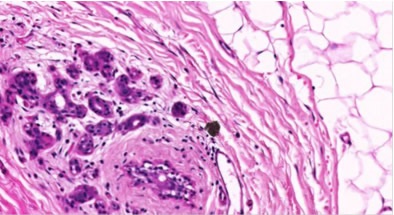

20X magnification of breast tissue specimen with 0.5μm resolution

Figure 2. 20X magnification of breast tissue specimen with 0.5μm resolution. Image credit: Huron Digital Pathology.